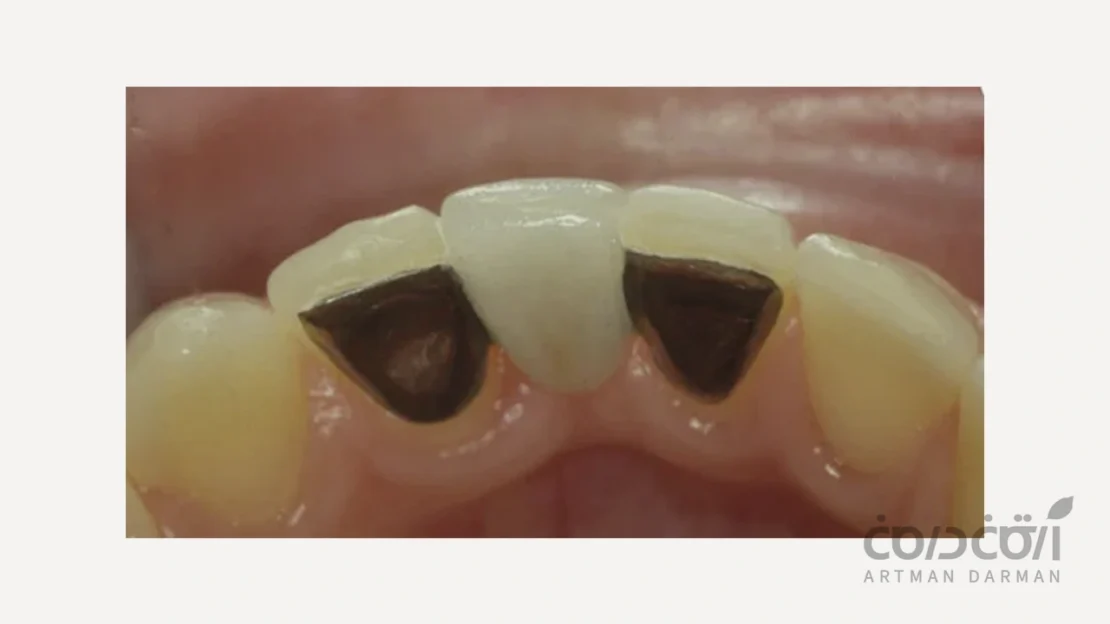

مریلند از نظر ساختار در واقع یک دندان مصنوعی از جنس کامپوزیت یا آکریلیک که دارای دو باله کوچک در طرفین است. این باله ها با استفاده از چسب های دندانپزشکی (رزین باندینگ) به پشت دندان های سالم مجاور چسبانده می شوند.

دو مورد از بهترین مزایای بریج مریلند عبارتند از:

- از آنجایی که ثابت است، حس آن بسیار شبیه به دندان طبیعی است. و هنگام صحبت کردن یا لبخند زدن هیچ نگرانی از بابت جابجایی وجود ندارد.

- هیچ جزء خارجی قابل مشاهده ای ندارد.

چیزهایی که باید در خصوص مریلند بدانید هم به شرح زیر است:

- موفقیت آن به کیفیت چسبندگی به دندان های کناری بستگی دارد و ممکن است گاهی اوقات شل شود.

- تمیز کردن زیر آن نیازمند استفاده از نخ دندان مخصوص (Superfloss) است.

- این نوع پروتز موقت ایمپلنت تنها برای جایگزینی یک دندان مناسب است.